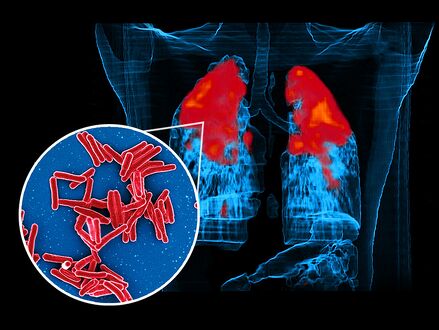

Scanning electron micrograph of Mycobacterium tuberculosis bacteria, which cause TB foreground image and a PET/CT scan showing TB infection (red) in an individuals lungs background image

In active pulmonary TB, infiltrates or consolidations and/or cavities are often seen in the upper lungs with or without mediastinal or hilar lymphadenopathy or pleural effusions ( tuberculous pleurisy). However, lesions may appear anywhere in the lungs. In disseminated TB a pattern of many tiny nodules throughout the lung fields is common - the so-called miliary TB. In HIV and other immunosuppressed persons, any abnormality may indicate TB or the chest X-ray may even appear entirely normal.[citation needed]

FDG PET/CT can play several useful roles in patients with confirmed or suspected TB.[8] These roles include detection of active TB lesions, assessment of disease activity, differentiation between active and latent disease, assessment of disease extent (staging), monitoring response to treatment, and identification of potential biopsy target.[8]